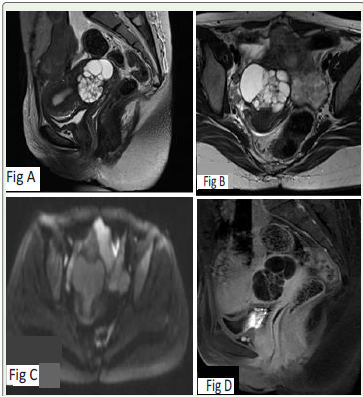

cystic lesion within the cervix. Pelvic MRI was subsequently

performed, showing an enlarged cervix with a multiloculated cystic

lesion that was T2 hyperintense and T1 hypointense, extending

into the deep stroma. Post-contrast imaging demonstrated thick

enhancing septa [Figure 1].

Figure 1:A and B – T2 sagittal and oblique axial images showing enlarged

cervix with a multiloculated cystic lesion measuring 4.2 x 6.3x 4.7cm with involvement of deep cervical stroma

C – No diffusion restriction.

D – Post contrast sagittal images showing thick enhancing septa and wall.

No definite solid component.